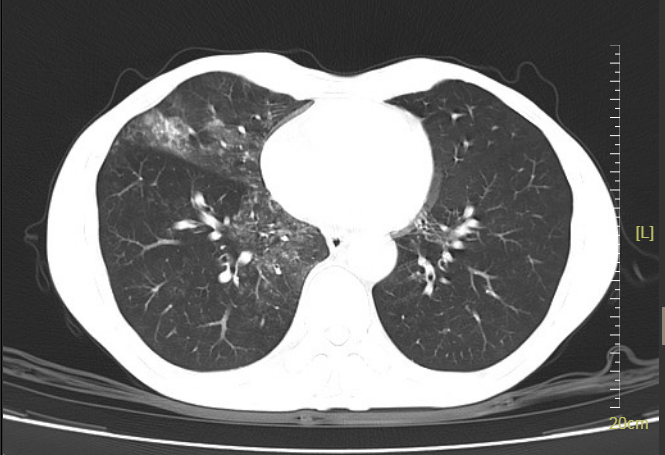

51岁的李先生(化名)10余年前接受鼻咽癌放疗,近2年反复出现饮水呛咳,进食困难,尤其进食固体食物时梗阻感明显,须“水捞饭”才能勉强进食。更为严重的是,这一年他已经经历了两次重症肺炎(CT见下图),差点进了ICU。张先生百思不得其解,在呼吸科医生的推荐下,来到了康复医学科门诊。

通过吞咽造影检查,李先生的问题终于“水落石穿”——是“吞咽障碍”惹的祸!

▲李先生存在环咽肌开放不完全,会厌谷和梨状窦大量残留,并且存在明显误吸,因此导致反复重症肺部感染。